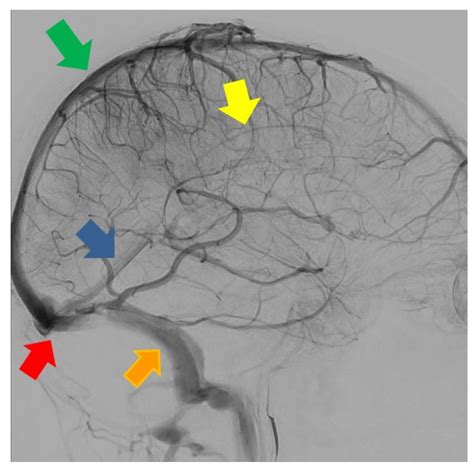

Preoperative imaging, including magnetic resonance venography (MRV) and computed tomography venography (CTV), can help identify the Inferior Sagittal Sinus and plan the surgical approach accordingly.

Diagnostic Imaging

Diagnostic imaging plays a crucial role in evaluating the Inferior Sagittal Sinus. Techniques such as MRV and CTV provide detailed visualization of the venous sinuses, allowing for the detection of abnormalities and pathologies. Common pathologies that can affect the Inferior Sagittal Sinus include:

Diagnostic imaging is the cornerstone of evaluating the Inferior Sagittal Sinus. The following imaging modalities are commonly used:

• Magnetic Resonance Venography (MRV): Provides detailed visualization of the venous sinuses without the use of ionizing radiation. It is particularly useful for detecting thrombosis and other venous abnormalities.

• Computed Tomography Venography (CTV): Offers high-resolution images of the venous sinuses and is useful for detecting acute thrombosis and other pathologies.

• Digital Subtraction Angiography (DSA): Provides real-time visualization of the venous sinuses and is often used for interventional procedures.

In addition to imaging, clinical evaluation and laboratory tests may be necessary to assess the patient's overall condition and identify any underlying causes of the pathology.